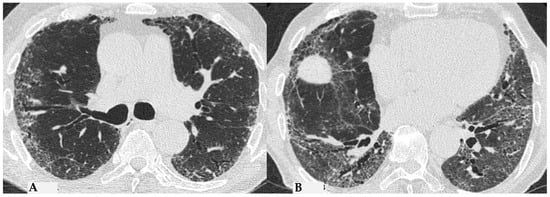

Figure 8.

Axial chest HRCT scan. Asymmetric fibrotic alterations with volume loss on the right in the upper lobe (A); in the lower lobes on the right, a significant extensive area of reduced attenuation is evident, suggestive of air trapping (red box), with components of distorted GGO and fibrosing characteristics with intra- and interlobular thickening and traction bronchiectasis/bronchiolectasis (B).